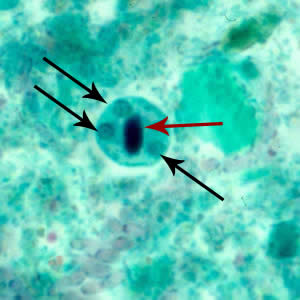

E.histolytica cyst

four nuclei and a chromatoid body with blunt ends